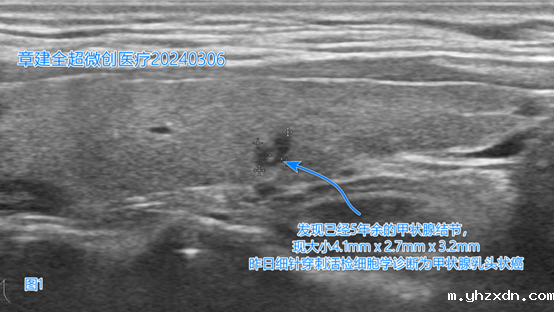

经过全面、细致的检查,我们发现他甲状腺右叶腺体全部正常,左叶腺体大部正常,左叶腺体内仅可见一枚4.1mmx2.7mmx3.2mm大小的结节,超声影像的确更像是乳头状癌(图1)。